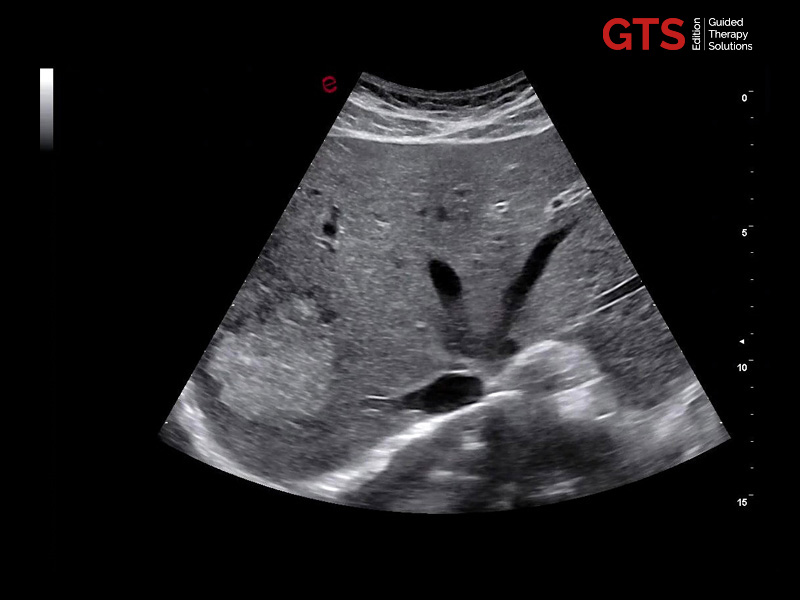

Daily prostate examinations: Trans-Perineal Ultrasound (TPUS) and Trans-Rectal Ultrasound (TRUS) approaches

In daily practice, high image quality and ease of use of advanced features (with fast and automatic measurements) make the difference.

Our new urology solutions enhance the user experience and increase confidence by offering the option of performing detailed prostate examinations with either TRUS or TPUS biopsy approaches, thanks to our end-fire or bi-plane transducers. Each probe is compatible with tailored biopsy guides, either reusable or single use.

Prostate in axial view using E 3-12 - End-fire probe, E 3-12

Prostate in sagittal view using TLC 3-13 - Bi-planar probe, TLC 3-13